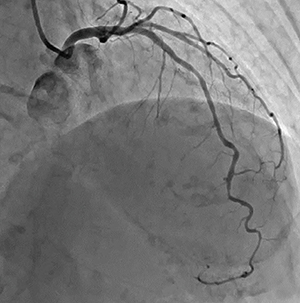

図2 ステント強調機能

“Stent Mode”を用いることで、ステントのエッジやオーバーラップが明瞭に表現されている。